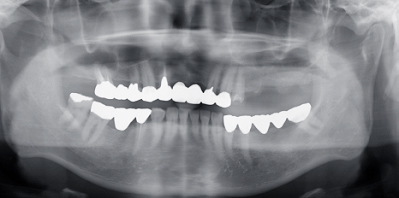

ご紹介で向かって右上奥歯が欠損してインプラントを希望された患者さんです。

治療前のパノラマエックス線像です。骨の状態が不鮮明でレントゲンの2次元の限界を感じます。